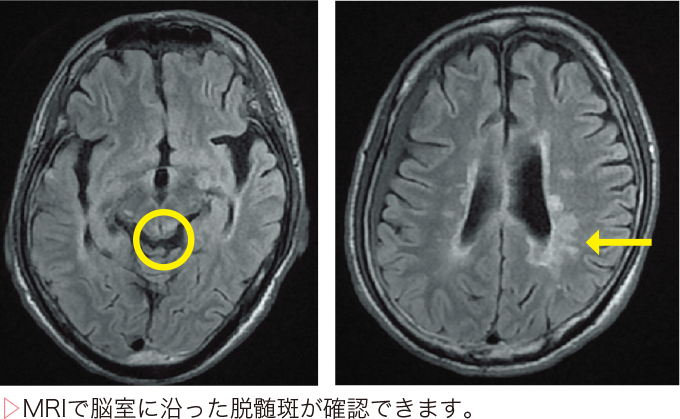

- MRIなどの画像検査を使用する